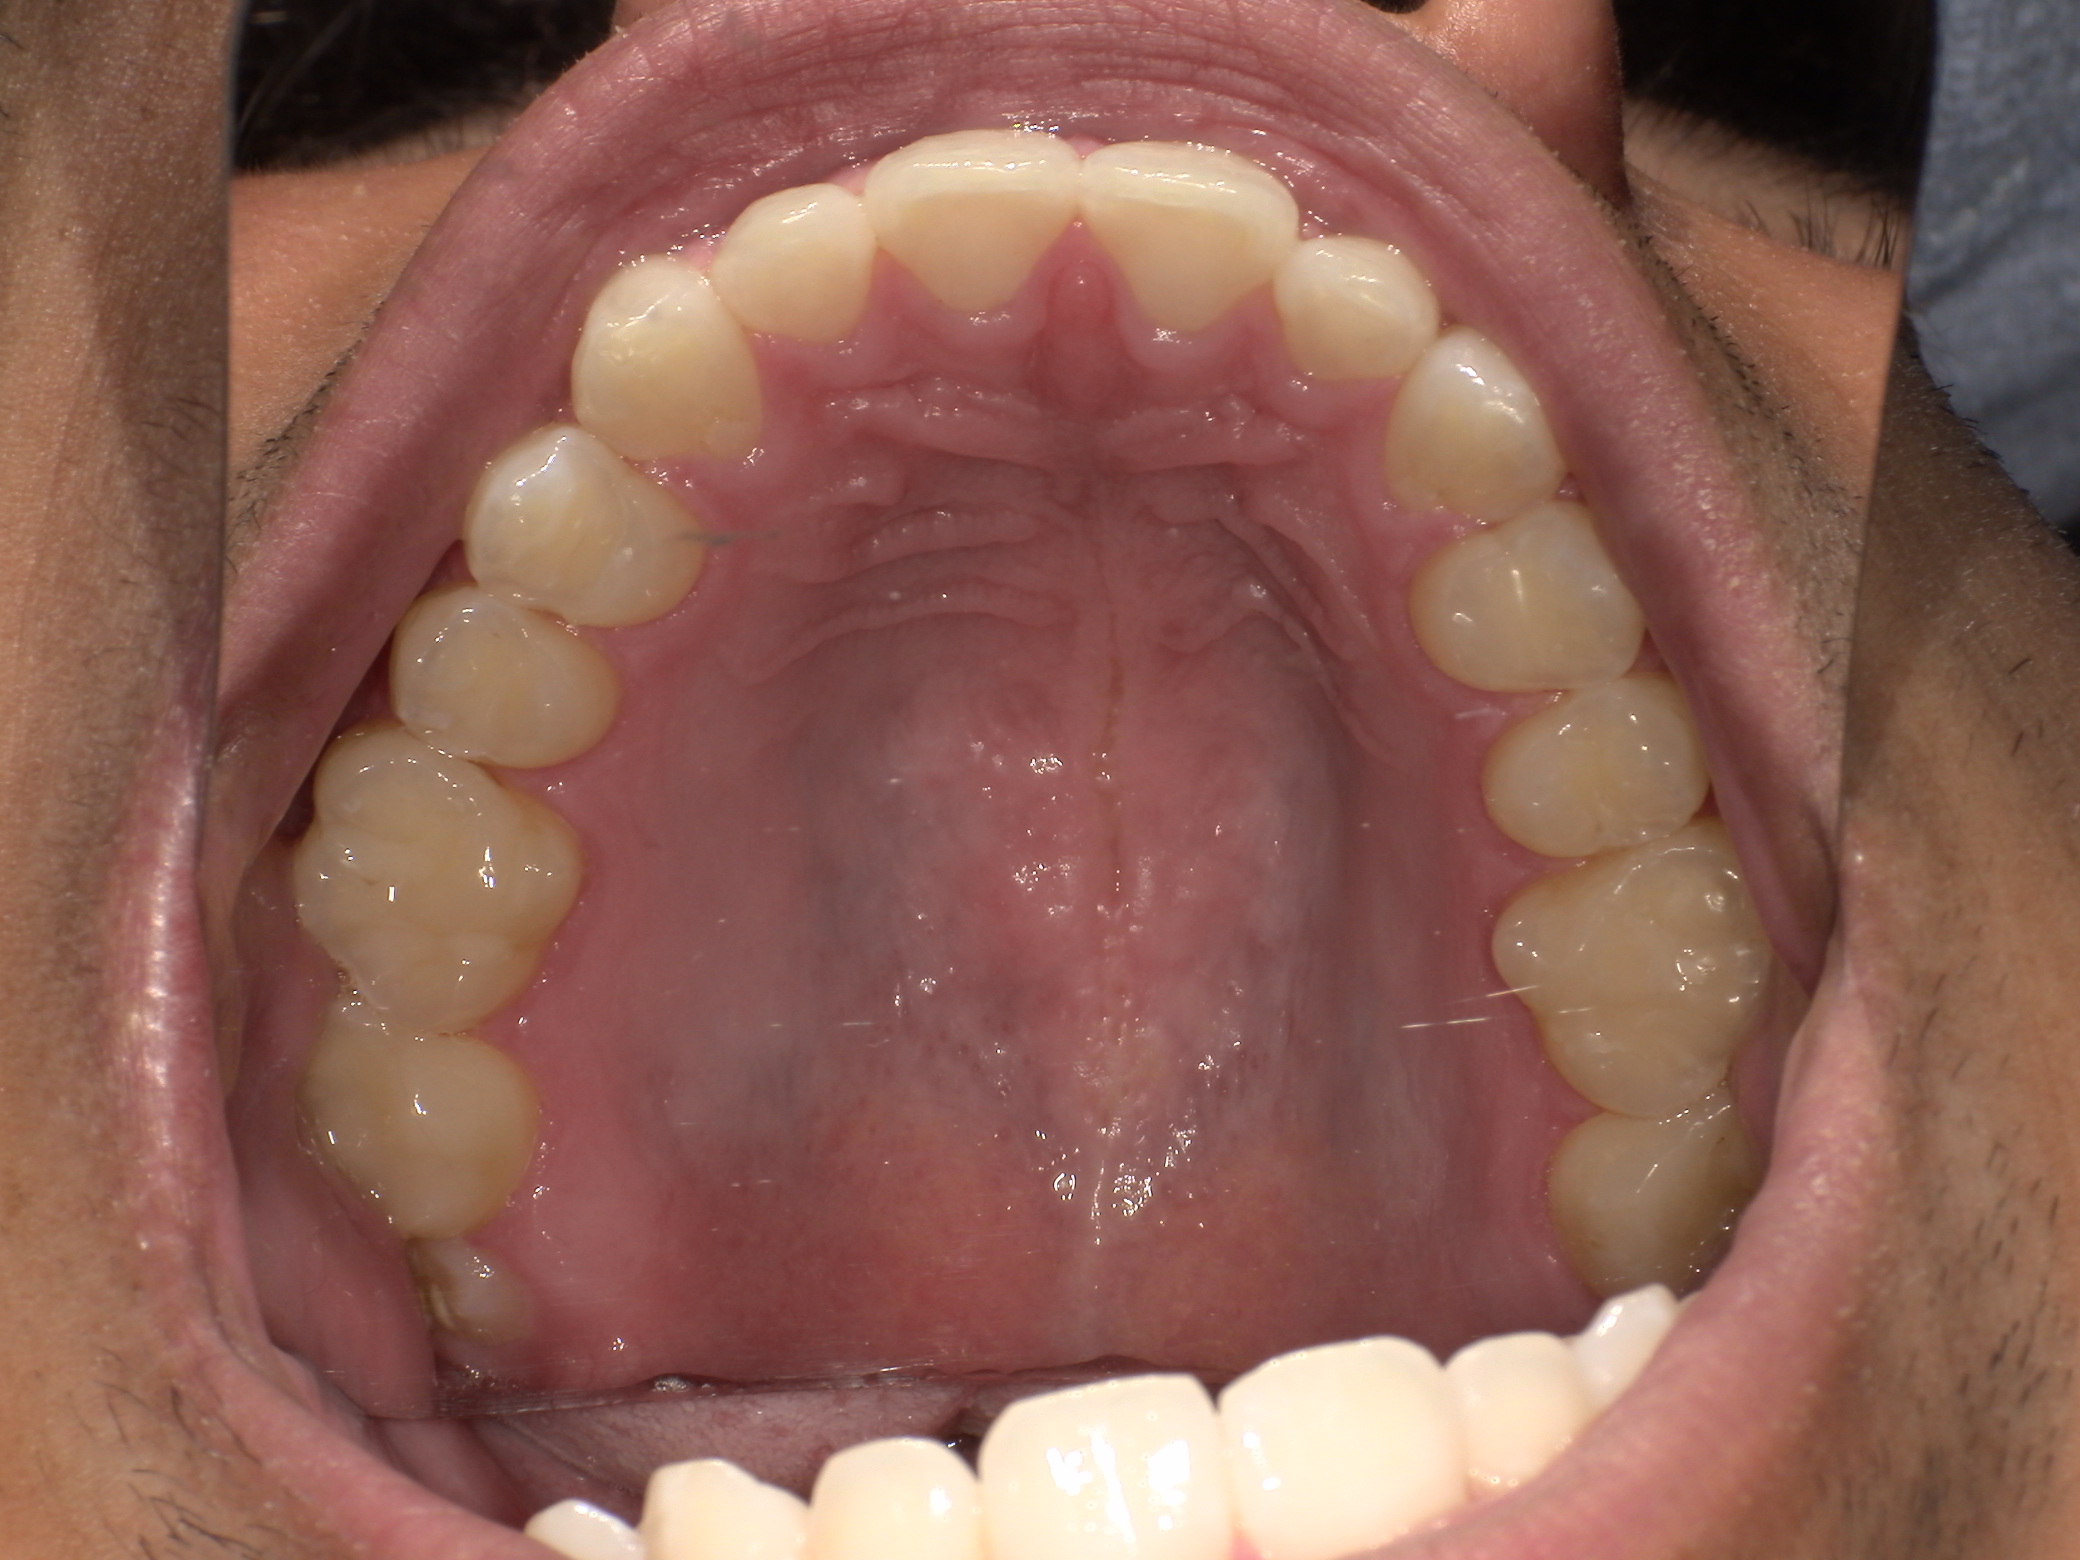

If you struggle with snoring, mouth breathing, poor sleep, fatigue, headaches, grinding, or focus issues, airway diagnostics can help identify root cause. It’s also valuable for children with crowded teeth, narrow arches, or sleep and behavior challenges.

Your evaluation includes a CT scan, comprehensive oral images, sleep assessment, and personalized treatment plan from Dr. Trivedi. If you choose to proceed with the complete solution stack, your evaluation costs will be applied as a discount.

After your evaluation, the doctor reviews your results and explains how your airway structures are impacting your health. You’ll then receive a personalized plan that may include palatal expansion, aligners, or other therapies to optimize your health.